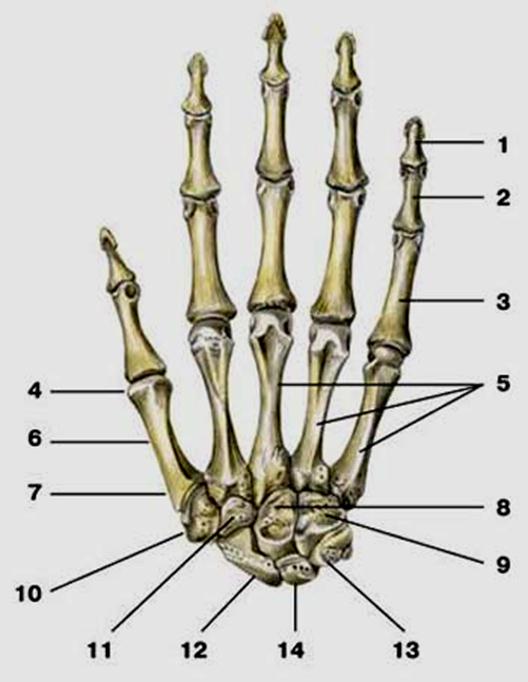

S: Числом 10 обозначена os ### (латинский язык).

S: Цифра 5 обозначает ossa ### (латинский язык).

S: Цифрой 8 обозначена os...

S: Числом 12 обозначена os...

S: Числом 13 обозначена os...

S: Цифра 3 указывает на...

S: Цифра 2 указывает на …

S: Цифра 1 указывает на....